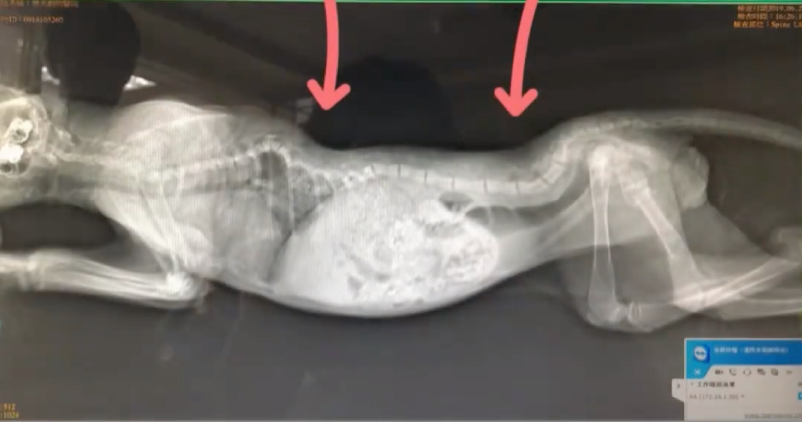

六年前,一隻虛弱的虎斑貓被發現倒在路邊,牠後腿癱瘓,身上還有潰爛的傷口。送往多家獸醫院後,診斷結果顯示牠脊椎重傷,肺部曾出血,存活機率渺茫。許多獸醫建議飼主讓牠安詳離開,但貓咪沒有放棄,依然努力進食求生。於是,飼主決定給牠一個家,取名阿吉,希望牠能帶著這份「吉祥」,迎來嶄新的貓生。

阿吉的後腿雖然無法動彈,但這並不妨礙牠向前邁進。從最初只能趴在地上,到努力用前腳拖動自己前行,牠的每一步都來之不易。剛開始移動時,阿吉總是吃力地抬起上半身,然後慢慢向前滑行,雖然步伐緩慢,卻從未停下探索的腳步。為了幫助阿吉適應新生活,飼主和爸爸還親手製作了一個支架,幫助牠進行復健。即使醫生診斷阿吉為最嚴重的5級癱瘓,他們依然選擇試一試,給牠一個站起來的機會。